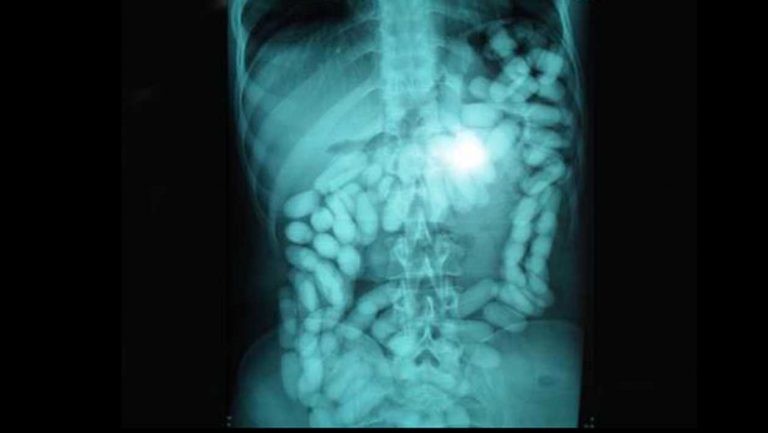

REYKJAVIK – Η ισλανδική αστυνομία ανέβασε μια φωτογραφία από τη σύλληψη ναρκωτικών που έκανε μέσα στο 2017. Το πιο περίεργο περιστατικό ήταν αυτό που βρήκαν στο στομάχι ενός βέλγου λαθρεμπόρου με ειδικές ανάγκες: ένα κιλό κοκαΐνης κρυμμένο στο στομάχι του.

Όταν ο Βέλγος έπρεπε να περάσει από τον έλεγχο, οι υπάλληλοι είδαν 106 λευκά σακουλάκια στα έντερα και στο στομάχι του. Ο Βέλγος παραδέχτηκε αργότερα ότι είχε καταπιεί τα σακουλάκια κοκαΐνης λίγο πριν από την απογείωση.